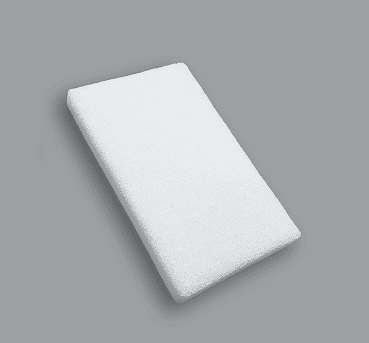

Block